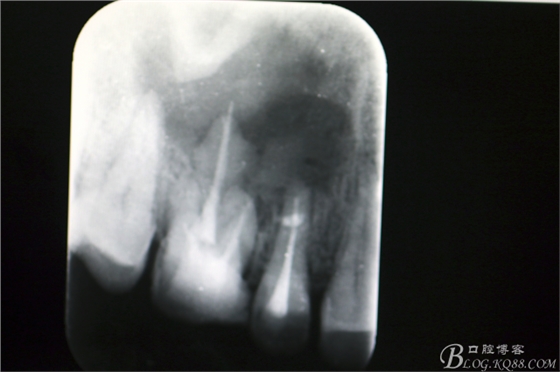

圖3.根尖片顯示15、16根管治療已經(jīng)完成,16腭根牙膠尖超填,15、16根尖區(qū)橢圓形陰影